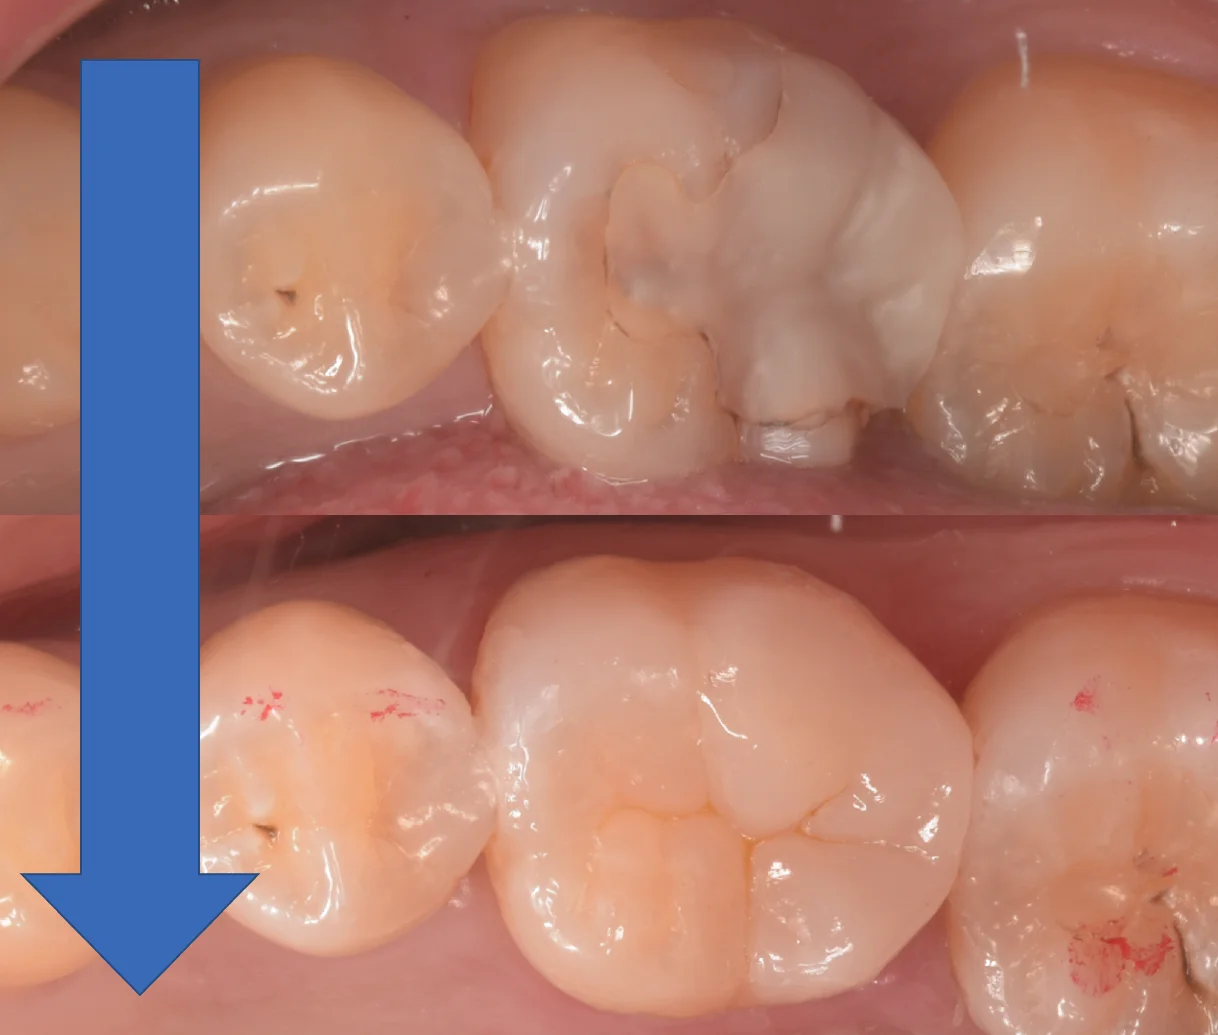

さて、古い詰め物を除去したのがこちらになります。

歯科医師の方のCAD/CAMインレーを治療。|坂寄歯科医院(取手市藤代) - 画像2

接着が不十分のため、非常に広範囲に虫歯になってしまっています。

ただこれが術直後から接着が不十分だったのか、上記の通り接着が難しい材料のため、経年により接着が失われたのかはこの場ではわかりません。

ただこの方のこの歯に関しては2〜3年で接着面からダメになったという事実だけがあるという感じですね。